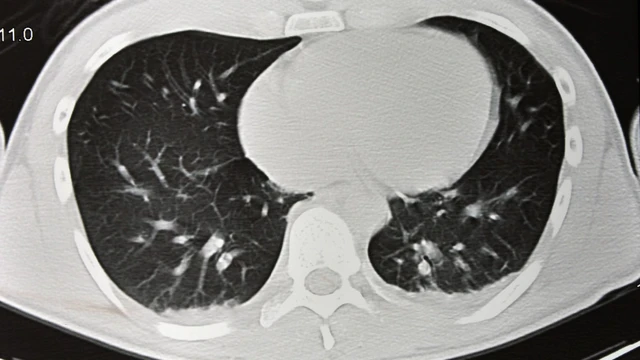

Chụp X-quang có phát hiện khối u không là thắc mắc phổ biến của nhiều người khi được bác sĩ chỉ định thực hiện kỹ thuật này. Đây là một trong những phương pháp chẩn đoán hình ảnh được sử dụng rộng rãi, giúp đánh giá tình trạng xương khớp, phổi và một số cơ quan khác trong cơ thể.